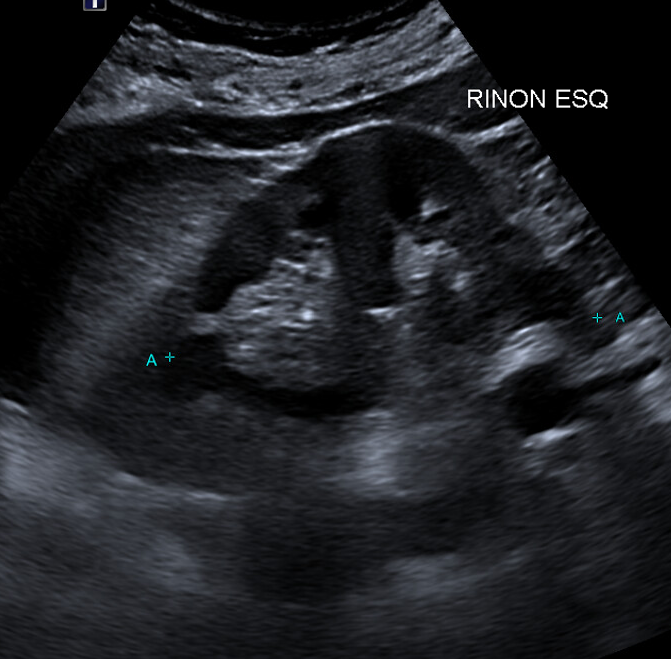

Hallazgos ecográficos

Riñón izquierdo, protuberancia en borde lateral del lóbulo medio, pseudomasa en tercio medio de riñón izquierdo con desplazamiento de la estructura cortical del riñón. Vejiga normal, replecionada, sin alteraciones ecográficas en su interior. Jets renales adecuados, sin alteraciones

La «joroba de dromedario» es una variante anatómica benigna del riñón izquierdo. Dada por una protuberancia focal en el borde lateral del riñón izquierdo, relacionada con una impronta esplénica. Junto con la hipertrofia de la columna de Bertin, pueden simular masas.